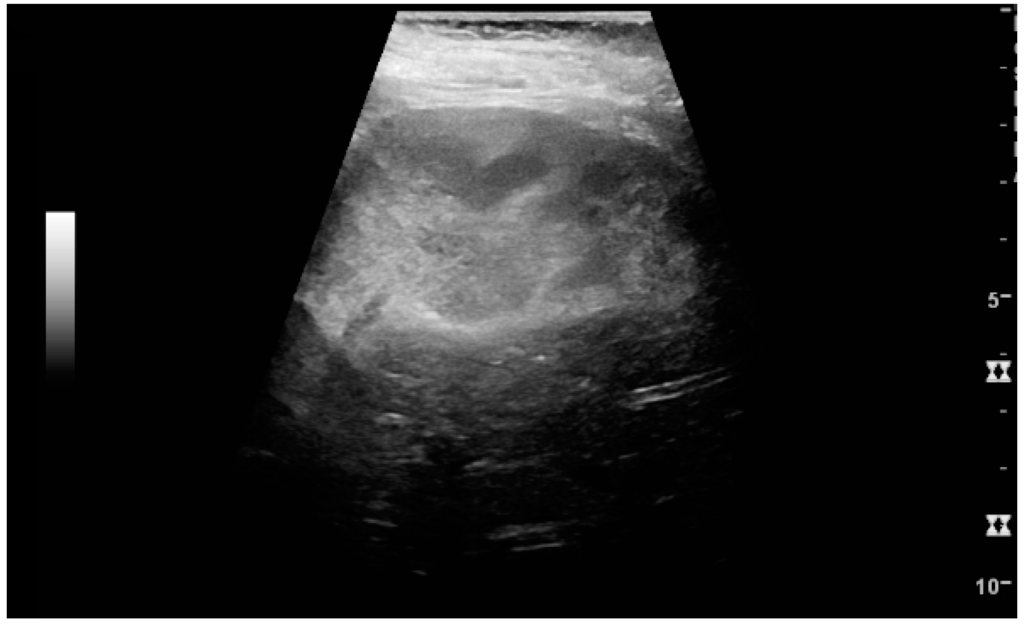

Figure 7. Advanced polycystic kidney disease with multiple cysts.